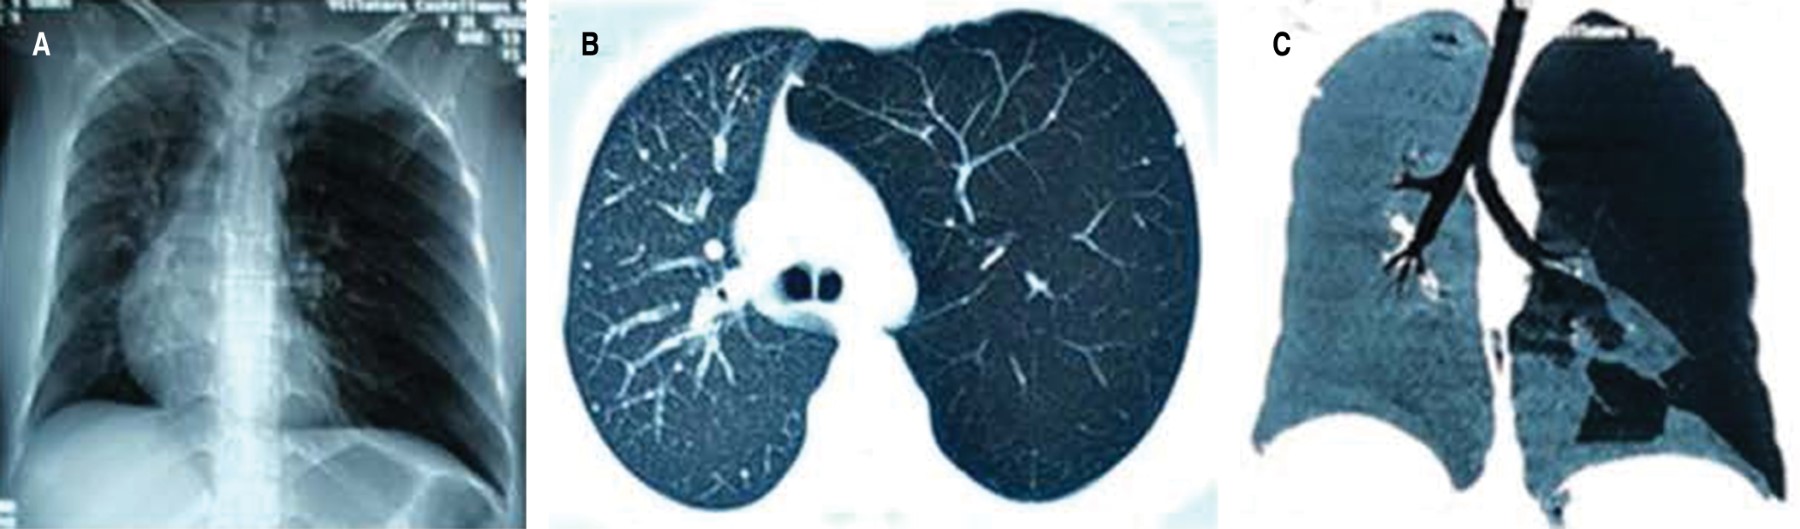

La radiografía de tórax mostró pulmón izquierdo sobredistendido, desplazando el mediastino hacia la derecha e hiperlúcido; en la tomografía axial computarizada (TAC) se observó, además, distribución anómala de la vasculatura pulmonar con áreas de hipoperfusión de distribución variable (Figura 1).

Un leve dolor en el tórax motivó su consulta y la radiografía mostró el pulmón izquierdo hiperlúcido. Se diagnostica con mayor frecuencia en la infancia, típicamente ocurre en niños menores de ocho años, antes que el pulmón haya completado el desarrollo y la maduración pulmonar.5 Puede cursar de forma asintomática hasta la edad adulta, presentarse con neumotórax espontáneo generalmente asintomático,2 o como condición poco frecuente de emergencia,3 como bula calcificada6 y con transfiguración placentaria del parénquima pulmonar.7 La radiografía y tomografía de tórax de la paciente, mostraron pulmón segmentario hiperlúcido con alteración de la vascularidad, lo que normalmente describen otros autores como hiperclaridad pulmonar unilateral o lobar, asociada a atrapamiento aéreo del pulmón hiperclaro durante la espiración.2,5,8 A fin de descartar el diagnóstico diferencial de tromboembolia pulmonar se solicitó angiotomografía, la cual demostró las anomalías anatómicas de la arteria pulmonar izquierda con un menor calibre y disminución del flujo. El patrón espirométrico evidenció proceso restrictivo. No se realizó gammagrafía pulmonar que pudiera mostrar la disminución de la ventilación del pulmón patológico secundario a cambios enfisematosos y una marcada disminución de la perfusión, como consecuencia del menor calibre de la arteria pulmonar.5,8 Por lo tanto, los criterios de diagnóstico para este síndrome requieren uno de los siguientes hallazgos: a) pérdida unilateral del volumen pulmonar con hiperlucencia demostrada por radiografía de tórax; b) reducción unilateral de la vascularización en una tomografía computarizada del tórax; y c) pérdida de perfusión unilateral en gammagrafía pulmonar con tecnecio-99m.1,2